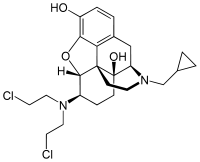

- Chlornaltrexamine

Chlornaltrexamine Chlornaltrexamine |